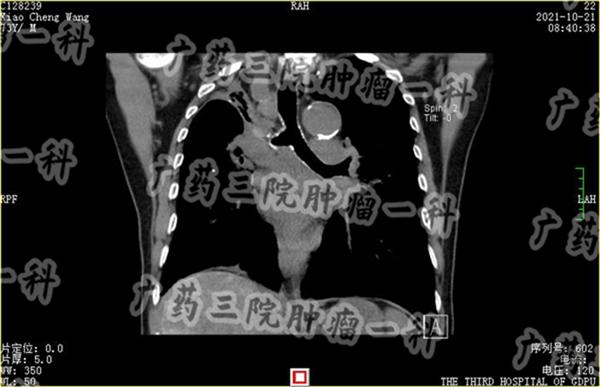

肺癌发展到IV期,很可能是已经出现了转移,有的患者甚至不止一处转移。此时的肺癌患者,开刀手术治疗效果有限,而且被癌细胞长时间掠夺营养,患者的身体状态下降,也难以承受开胸手术的副作用。

对这类患者,彭齐荣教授认为,患者可以进行微创综合治理。彭齐荣教授说,此时肺部的癌细胞已经开始扩散到远处,也是治疗最难的一个阶段,具体的治疗方案不能再是单一的某个治疗方式,而应该根据扩散的位置,患者的身体状况,来选择合适的技术,综合考虑,具体实施。

肺癌晚期可能出现肝转移,可能出现骨转移,可能出现淋巴转移等等,不同部位的转移病灶,合适的微创治疗方案不同,广药三院肿瘤科一区医生需要根据患者具体的转移部位,充分利用血管靶向治疗、粒子植入治疗、微波消融治疗、冷冻消融治疗等不同的微创治疗技术,制定合适的治疗方案。